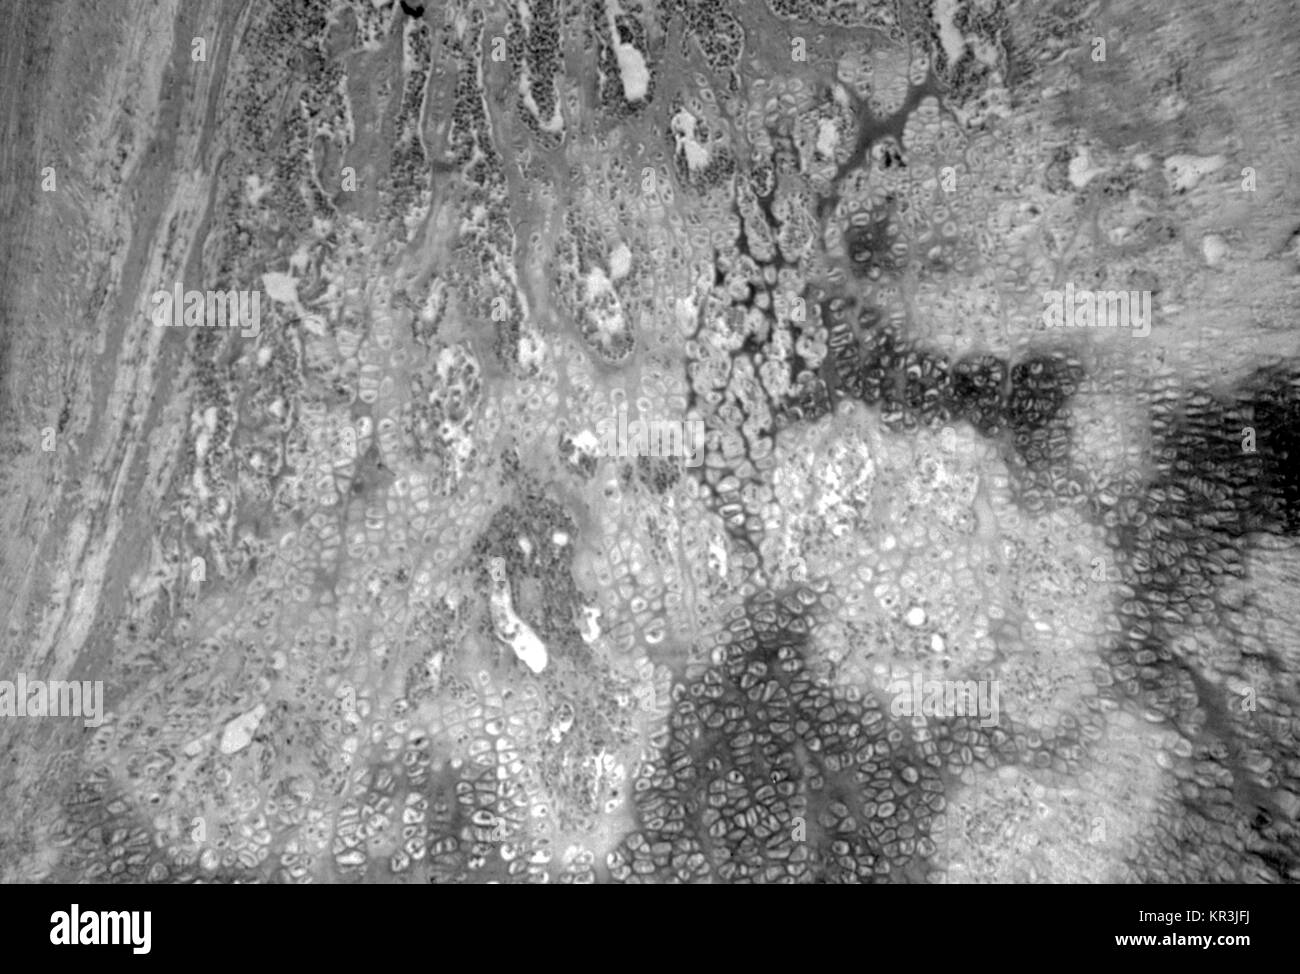

Una microfotografia di osteochondritis rivelando il cytoarchitectural cambia a causa della sifilide congenita. Vi è un marcato irregolarità nella zona provvisoria di ossificazione producendo un 'saw-dentata' aspetto, 1971. Nota le piccole isole di cartilagine rimanente nel ossificata osso, HandE macchia, ingrandimento 100X. Immagine cortesia CDC/Susan Lindsley. Foto Stockhttps://www.alamy.it/image-license-details/?v=1https://www.alamy.it/foto-immagine-una-microfotografia-di-osteochondritis-rivelando-il-cytoarchitectural-cambia-a-causa-della-sifilide-congenita-vi-e-un-marcato-irregolarita-nella-zona-provvisoria-di-ossificazione-producendo-un-saw-dentata-aspetto-1971-nota-le-piccole-isole-di-cartilagine-rimanente-nel-ossificata-osso-hande-macchia-ingrandimento-100x-immagine-cortesia-cdc-susan-lindsley-169110806.html

Una microfotografia di osteochondritis rivelando il cytoarchitectural cambia a causa della sifilide congenita. Vi è un marcato irregolarità nella zona provvisoria di ossificazione producendo un 'saw-dentata' aspetto, 1971. Nota le piccole isole di cartilagine rimanente nel ossificata osso, HandE macchia, ingrandimento 100X. Immagine cortesia CDC/Susan Lindsley. Foto Stockhttps://www.alamy.it/image-license-details/?v=1https://www.alamy.it/foto-immagine-una-microfotografia-di-osteochondritis-rivelando-il-cytoarchitectural-cambia-a-causa-della-sifilide-congenita-vi-e-un-marcato-irregolarita-nella-zona-provvisoria-di-ossificazione-producendo-un-saw-dentata-aspetto-1971-nota-le-piccole-isole-di-cartilagine-rimanente-nel-ossificata-osso-hande-macchia-ingrandimento-100x-immagine-cortesia-cdc-susan-lindsley-169110806.htmlRMKR3JFJ–Una microfotografia di osteochondritis rivelando il cytoarchitectural cambia a causa della sifilide congenita. Vi è un marcato irregolarità nella zona provvisoria di ossificazione producendo un 'saw-dentata' aspetto, 1971. Nota le piccole isole di cartilagine rimanente nel ossificata osso, HandE macchia, ingrandimento 100X. Immagine cortesia CDC/Susan Lindsley.